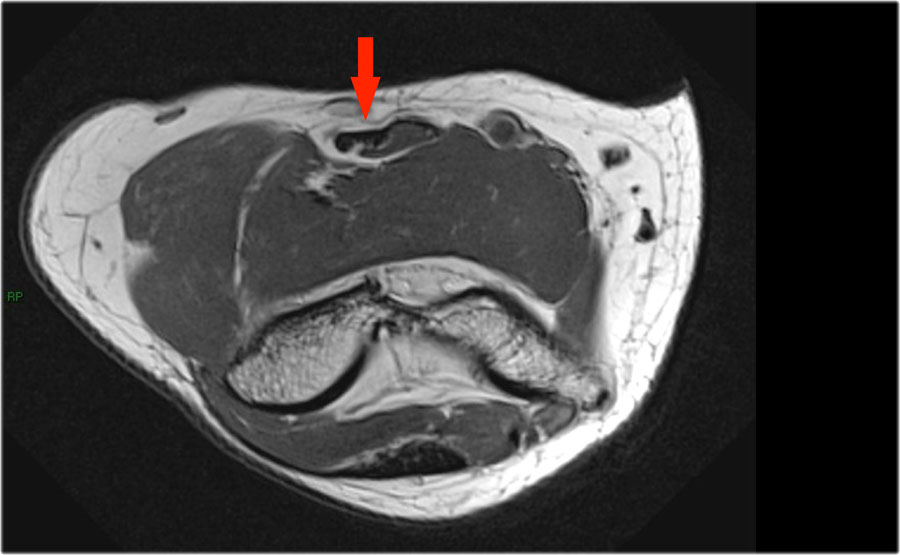

Những hình ảnh này của một nam giới 23 tuổi bị ngã chống tay khi đang trượt ván hai tuần trước.

Khi khám lâm sàng, ghi nhận giảm biên độ vận động khớp khuỷu và đau khi ấn dọc theo mặt ngoài.

Cấu trúc nào nằm phía sau chỏm quay trên hình ảnh cắt ngang?

Sagittal view:

- Một lần nữa, hình ảnh đặc trưng của phù tủy xương thường gặp trong trật khớp khuỷu tay ra sau với vết dập ở phía trước của chỏm xương quay (mũi tên đỏ) và ở phía sau của chỏm con xương cánh tay.

- Chỏm quay phải đã va chạm vào phần sau của chỏm con xương cánh tay.

Cấu trúc phía sau chỏm quay là dây chằng vòng.

Nó không đều và dày lên do hậu quả của trật khớp ra sau.